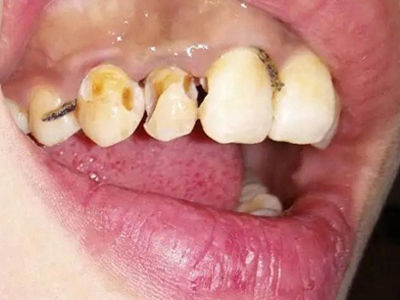

酸蚀症牙齿缺损严重有黄斑图

酸蚀症严重时可导致牙齿发生大块缺损,上门牙侧面有较大空洞,形似虫蛀,缺损处颜色明显发黄,呈黄褐色至深褐色,需积极进行牙齿修复治疗。

酸蚀症牙齿缺损发黑图

酸蚀症患者上门牙大部分缺失,累及周围牙体,牙釉质和牙本质出现大面积深度腐蚀破坏,牙颈部出现坑状缺损,露出黄褐色、黑色的缺损面牙体。